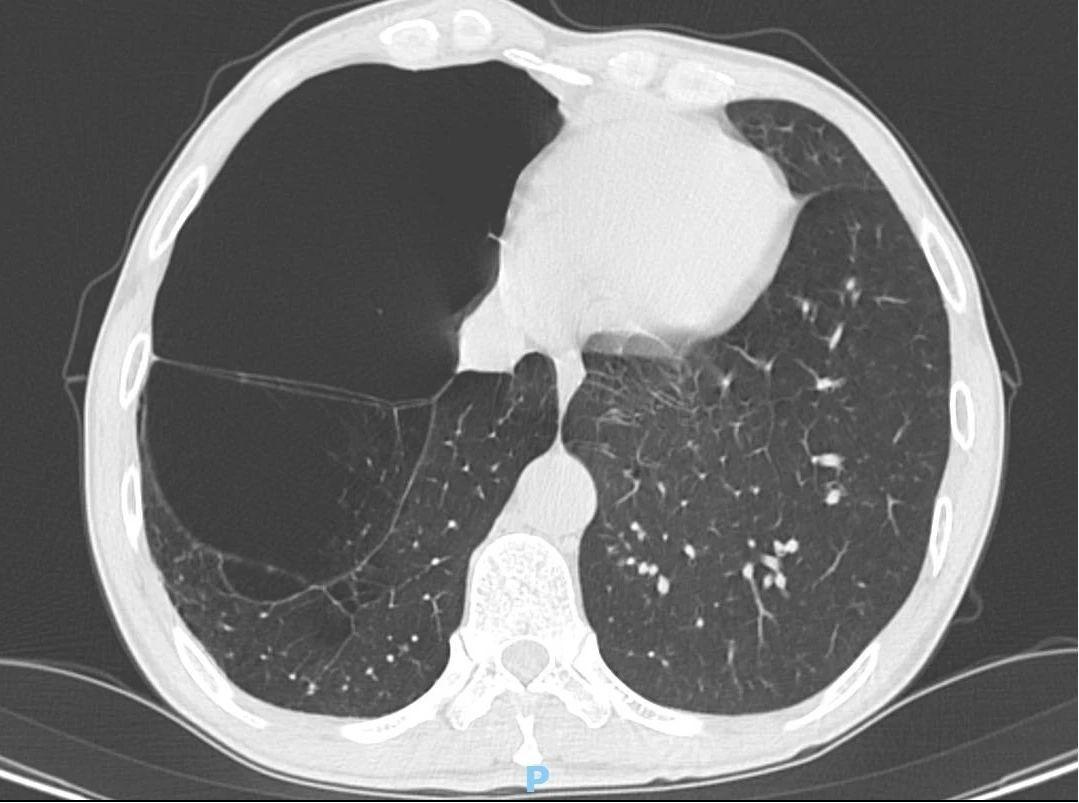

“来到医院时,患者不停地喘气。通过CT检查,发现他两侧的肺组织都长着像鱼泡一样的结构——被称为‘肺大泡组织’。”胸外科主任刘文粤说,患者右肺肺大泡相互融合,较大的约14.4cm*8.1cm,合并肺气肿及胸腔粘连。

陈旧性肺结核多发肺大泡

融合形成巨大肺大泡